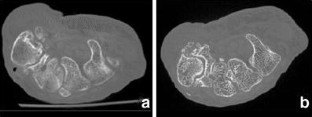

Flat-panel volume computed tomography (fpVCT) is a recent development in imaging. We discuss some of the musculoskeletal applications of a high-resolution flat-panel CT scanner. FpVCT has four main advantages over conventional multidetector computed tomography (MDCT): high-resolution imaging; volumetric coverage; dynamic imaging; omni-scanning. The overall effective dose of fpVCT is comparable to that of MDCT scanning. Although current fpVCT technology has higher spatial resolution, its contrast resolution is slightly lower than that of MDCT (5-10HU vs. 1-3HU respectively). We discuss the efficacy and potential utility of fpVCT in various applications related to musculoskeletal radiology and review some novel applications for pediatric bones, soft tissues, tumor perfusion, and imaging of tissue-engineered bone growth. We further discuss high-resolution CT and omni-scanning (combines fluoroscopic and tomographic imaging).